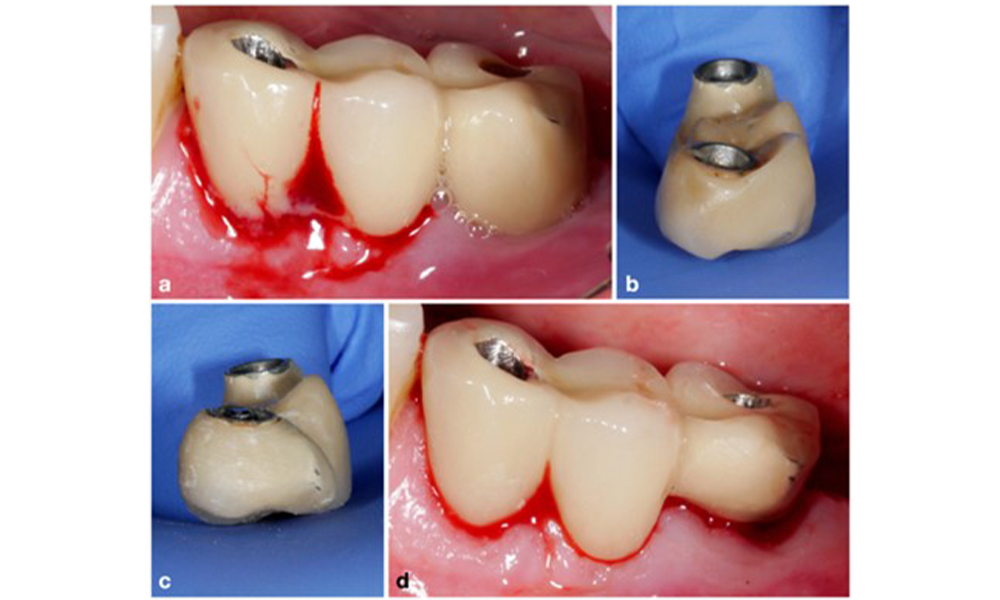

Thus, both the patient's oral hygiene routines and the prosthetic restoration’s design and implant positioning should support effective cleaning. If required, adjustments to the existing restoration (figure 5) and specific instructions for tailored oral hygiene measures are essential (figure 6) (Hamilton et al. 2023; Jepsen et al. 2015).

Modification of an existing bridge restoration. If the restoration hinders sufficient oral hygiene measures (notice the extreme overhang on the buccal aspect of the molar) (a–b), one of the first treatment steps should be adjusting the prosthetic design to enable effective cleaning (c–d).

Figure 5. Modification of an existing bridge restoration. If the restoration hinders sufficient oral hygiene measures (notice the extreme overhang on the buccal aspect of the molar) (a–b), one of the first treatment steps should be adjusting the prosthetic design to enable effective cleaning (c–d).